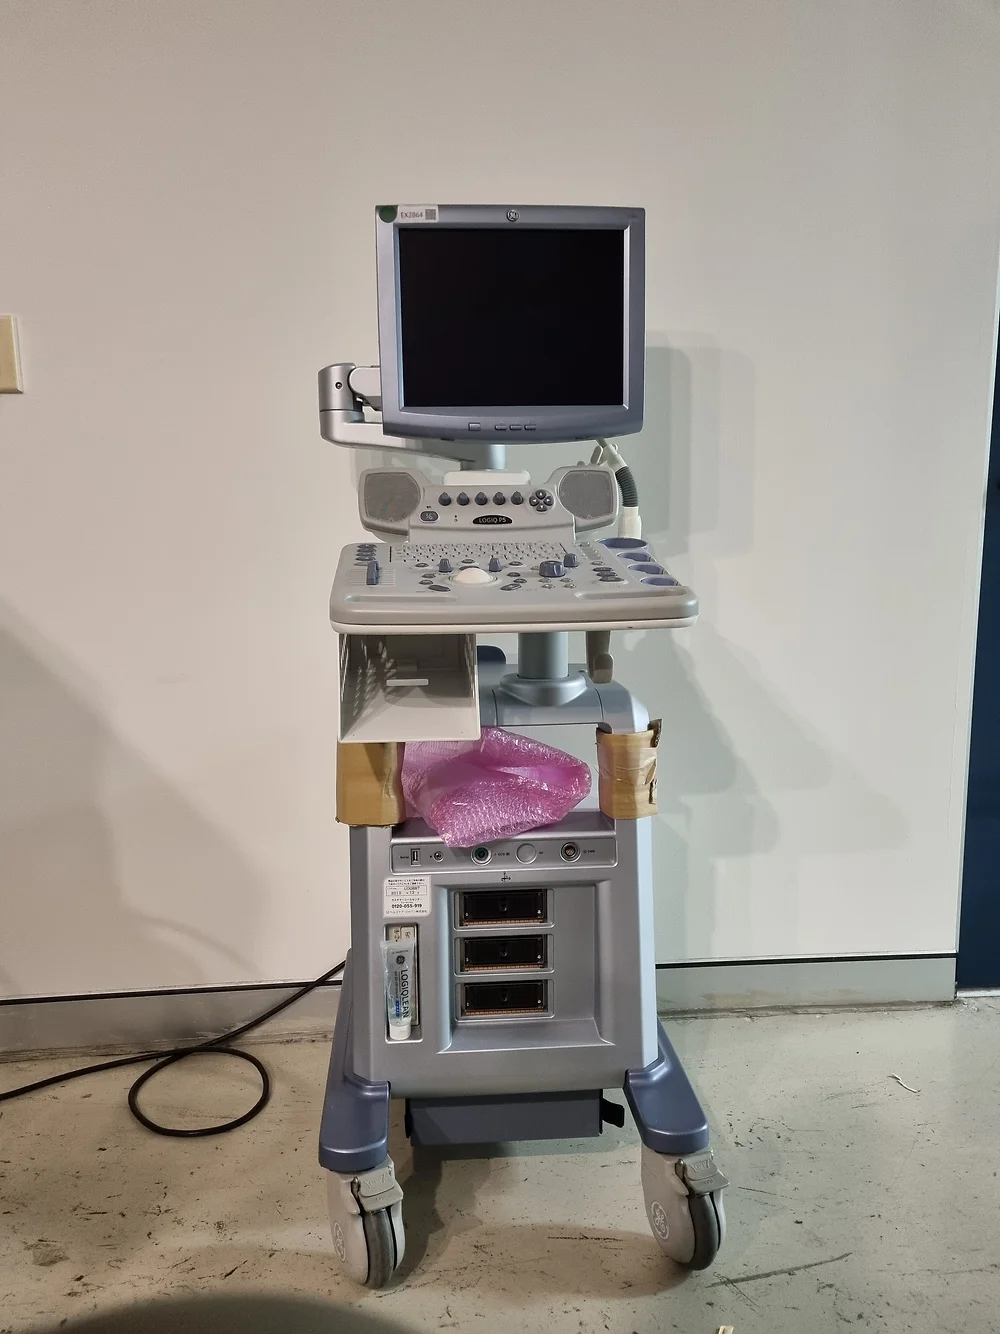

Unleashing Excellence: Introducing the LOGIQ P5 Ultrasound System

Elevating Imaging Standards: Unmatched Performance at a Remarkable Value

The LOGIQ P5 ultrasound system redefines compactness and efficiency while boasting a plethora of high-end features typically found in more expensive devices. Engineered for versatility and precision, this cutting-edge ultrasound scanner delivers unparalleled imaging quality across various medical specialties, including gynaecology/obstetrics, urology, cardiology, and paediatrics.

Key Features That Set the LOGIQ P5 Apart:

- Advanced Imaging Capabilities: Experience the power of 3D/4D imaging with the LOGIQ P5, enabling clinicians to obtain detailed and comprehensive insights into anatomical structures and pathology.

- Exceptional Performance: Despite its compact size, the LOGIQ P5 stands out as one of the most robust systems in its price range, offering features like CrossXBeam composite imaging, cardiac imaging, and speckle reduction for superior diagnostic accuracy.

- Enhanced User Experience: Navigate seamlessly through procedures with the LOGIQ P5’s intuitive interface and ergonomic design, ensuring optimal comfort and efficiency during imaging sessions.

- Efficient Data Management: Benefit from ample storage capacity with a 50 GB hard disk for image storage, enabling healthcare providers to efficiently manage and archive diagnostic data for future reference.

- Comprehensive Imaging Solutions: From automatic tissue optimization to coded harmonic imaging and high pulse repetition rate, the LOGIQ P5 is equipped with a range of innovative technologies to enhance imaging performance across diverse clinical applications.

Experience the pinnacle of ultrasound imaging technology with the LOGIQ P5 system. Whether you’re conducting routine examinations or complex diagnostic procedures, trust in the LOGIQ P5 to deliver unmatched performance and reliability at an exceptional value.